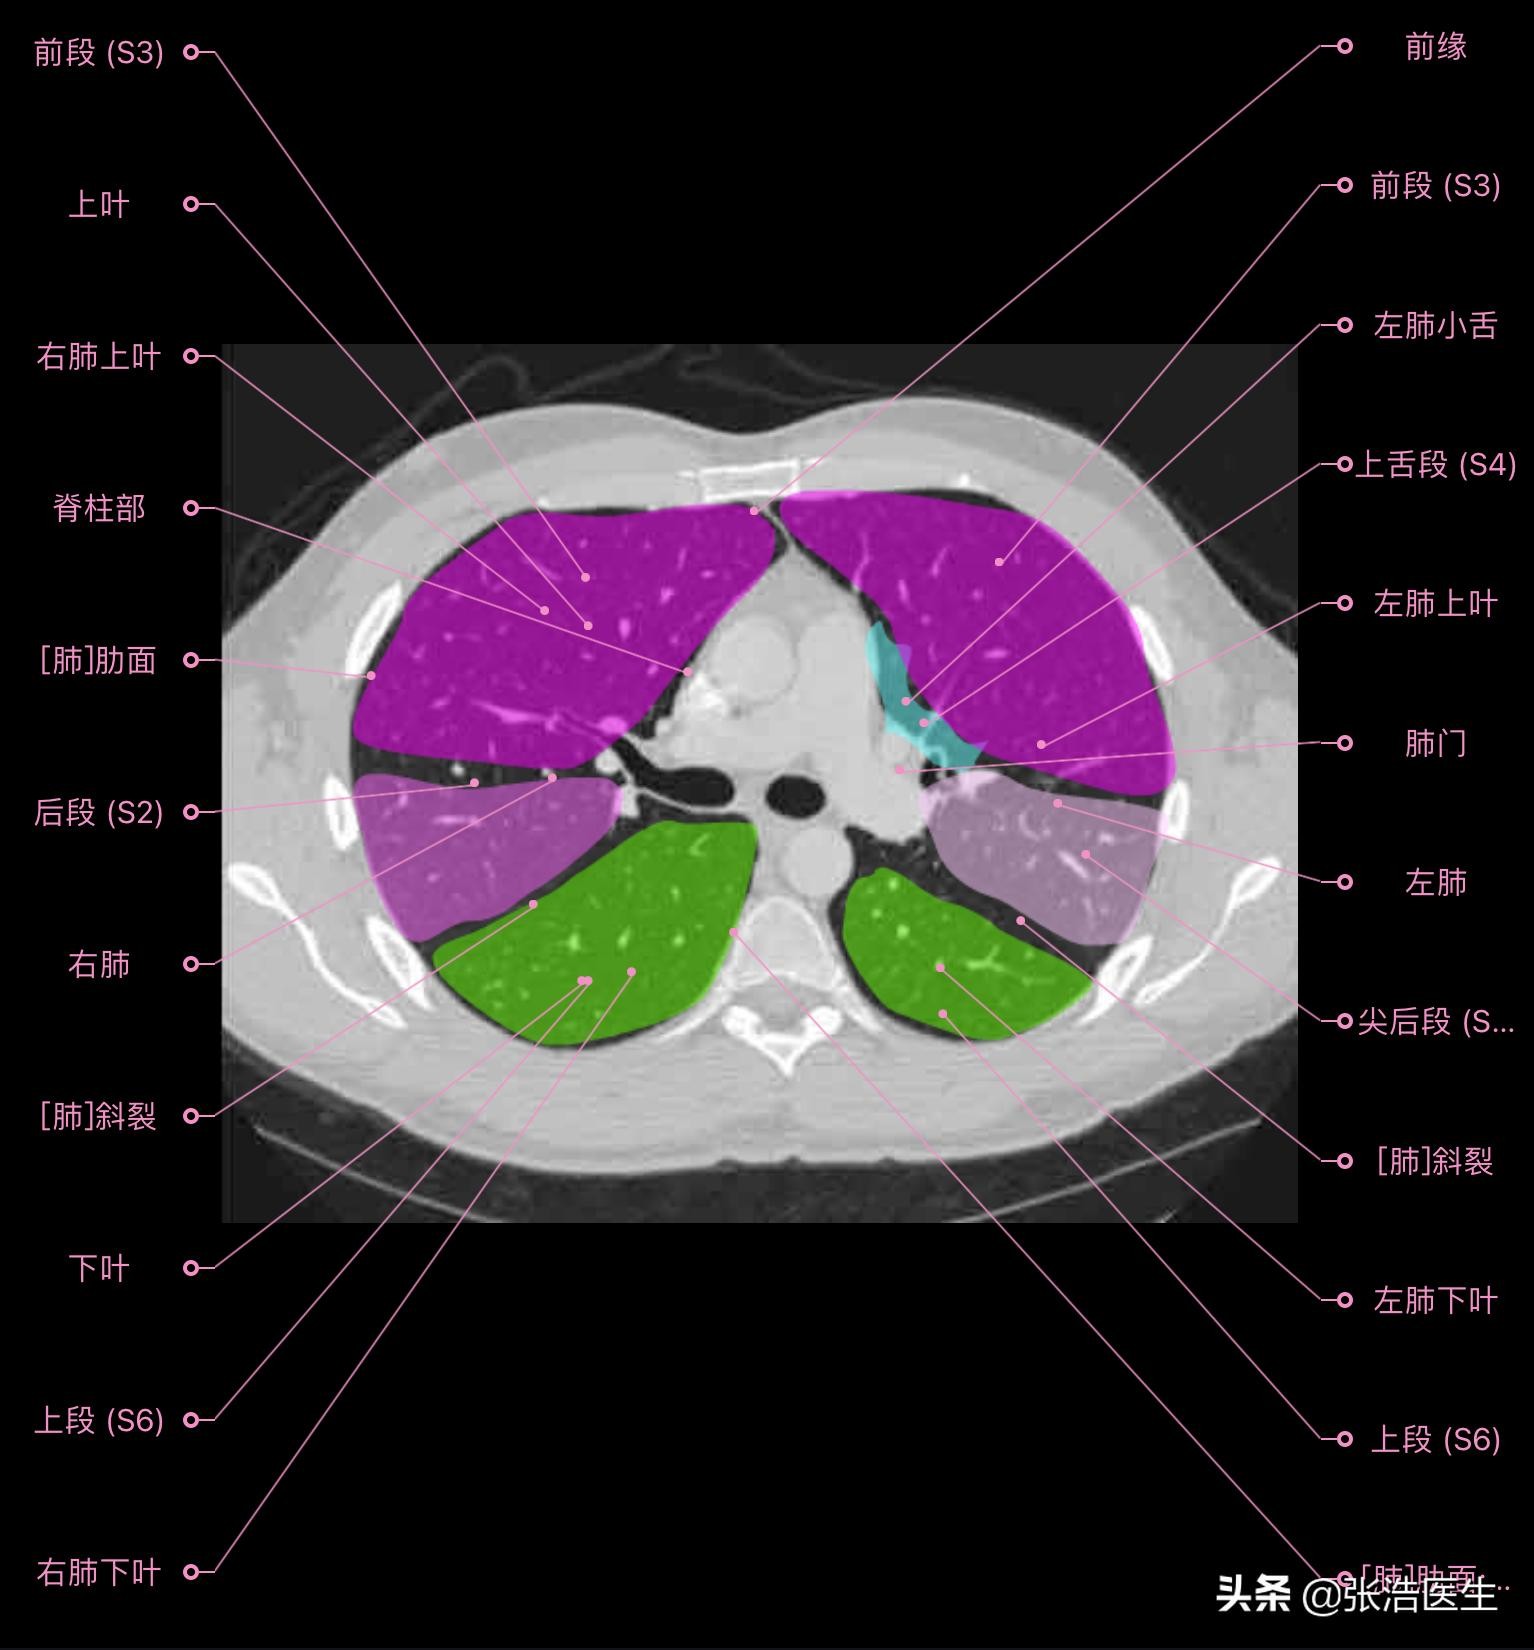

肺部CT横断面高清解剖图谱(图层1)

肺部CT横断面 高清解剖图谱

精选15层常用解剖断面

每一层都带有详细标注,值得收藏学习!